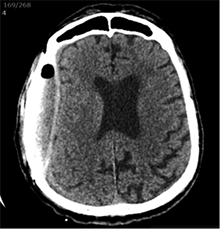

53 m. vyras sumuštas gatvėje ir greitosios medicinos pagalbos atvežtas į Priėmimo skyrių. Pacientui atlikta galvos kompiuterinė tomografija (GKT). Rasta: poūmė, stora, apie 16 mm dydžio subdurinė hematoma (SDH) dešinėje pusėje konveksitaliai ir ūmi nedidelė SDH kairėje pusėje frontoparietaliai. Vidurio struktūrų dislokacija (VSD) į kairę – minimali. Kairėje – kaukolės skliauto linijinis lūžis. Nustatyta nosies kaulų, nosies pertvaros, dešiniojo viršutinio žandikaulio kaktinės ataugos ir kūno, sinuso sienelių lūžių, dešinės akiduobės medialinio krašto lūžių ir dešiniojo skruostinio lanko lūžių (1 pav.). 2020 m. liepos mėn. pacientas skubos tvarka operuotas: atlikta dešinė kraniotomija, pašalinta hematoma. Atlikus kontrolinę GKT, buvo matyti, kad pašalinta didžioji hematomos dalis (2 pav.). Pacientas konsultuotas veido ir žandikaulio chirurgo, skubus chirurginis gydymas neindikuotas. Praėjus 3 savaitėms, pacientas, esant gerai funkcinei ir neurologinei būklei, tolesnio gydymo perkeltas į slaugos ligoninę, vėliau išleistas gydytis ambulatoriškai.

1 pav. Prieš pirmąją operaciją (poūmė, stambi, iki 16 mm SDH apie dešinįjį pusrutulį, ūmi nedidelė SDH kairėje F-P; VSD į kairę ~3 mm)